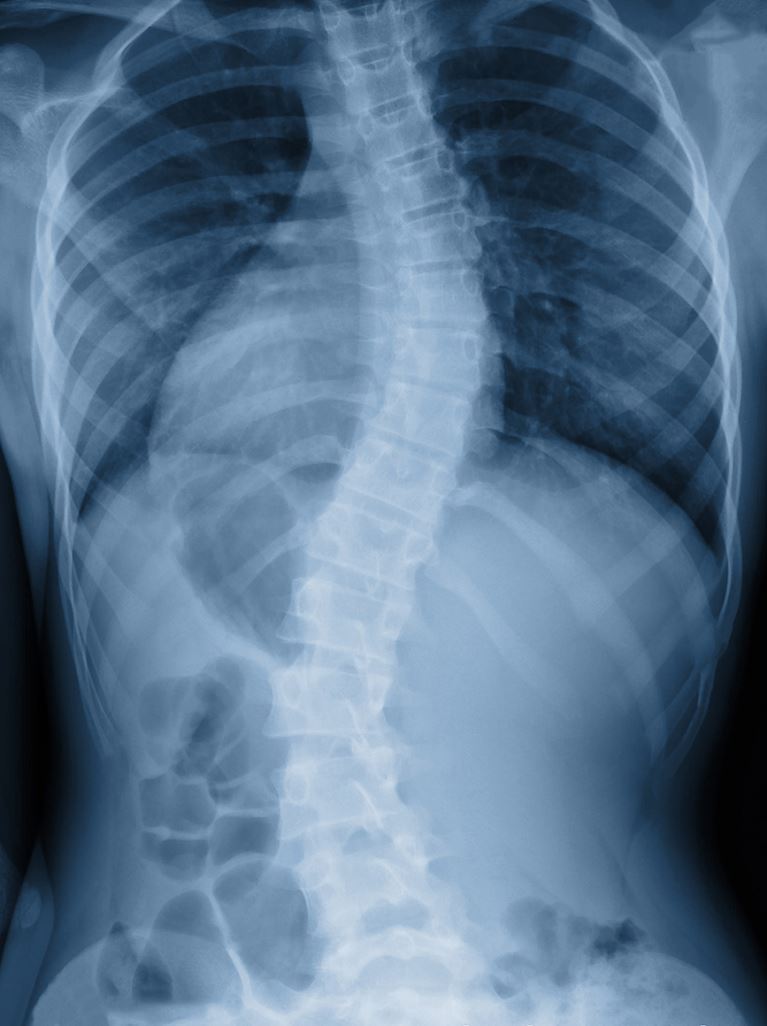

Scoliosis is the most common type of spinal deformity. Scoliosis is when the spine is abnormally curved. There are several types of scoliosis found in children, the most common of which is adolescent idiopathic scoliosis (AIS). AIS impacts approximately 5% of the population.

Adolescent idiopathic scoliosis (AIS) is an abnormal curve (“S” or “C” shape) of the spine that appears in late childhood or during the adolescent growth spurt. It typically affects children who have no other medical problems. While a family history of scoliosis is common, AIS patients often do not have other family members with the condition.